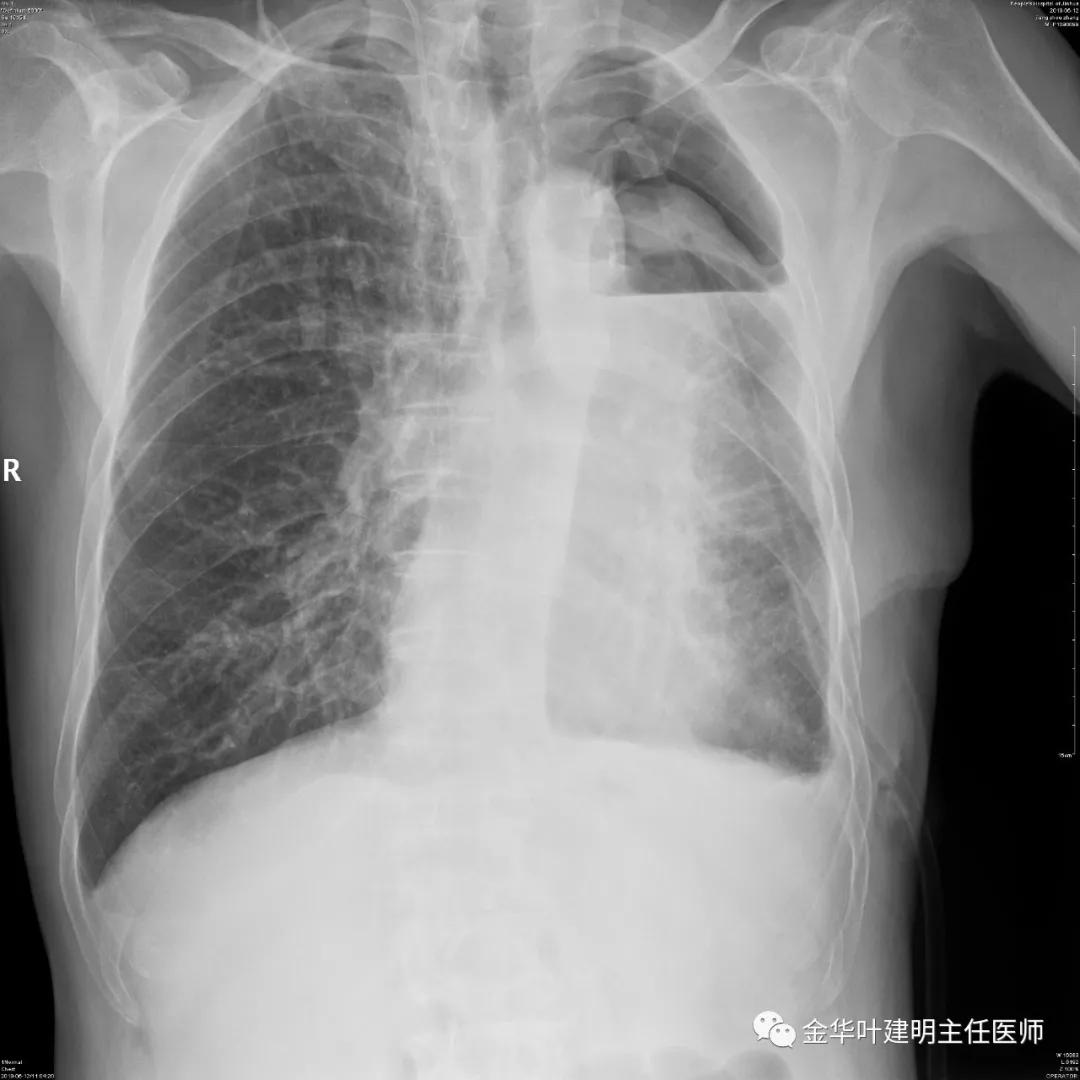

6.12上午:血红蛋白HGB:94 g/l;开放胸管引流出淡血性液400毫升后重新夹管;复查胸片示: